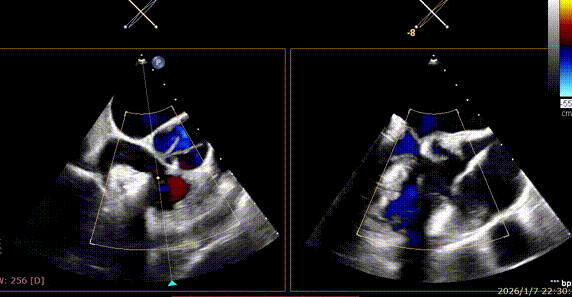

Annuloplasty Effect: The tricuspid valve annulus area was reduced from 9.96 cm² to 4.6 cm², representing a 53% decrease in annulus area.

Preoperative regurgitation (severe)

Postoperative regurgitation (trivial)

Surgical Outcome: Severe tricuspid regurgitation (4+) was reduced to mild tricuspid regurgitation (1+).